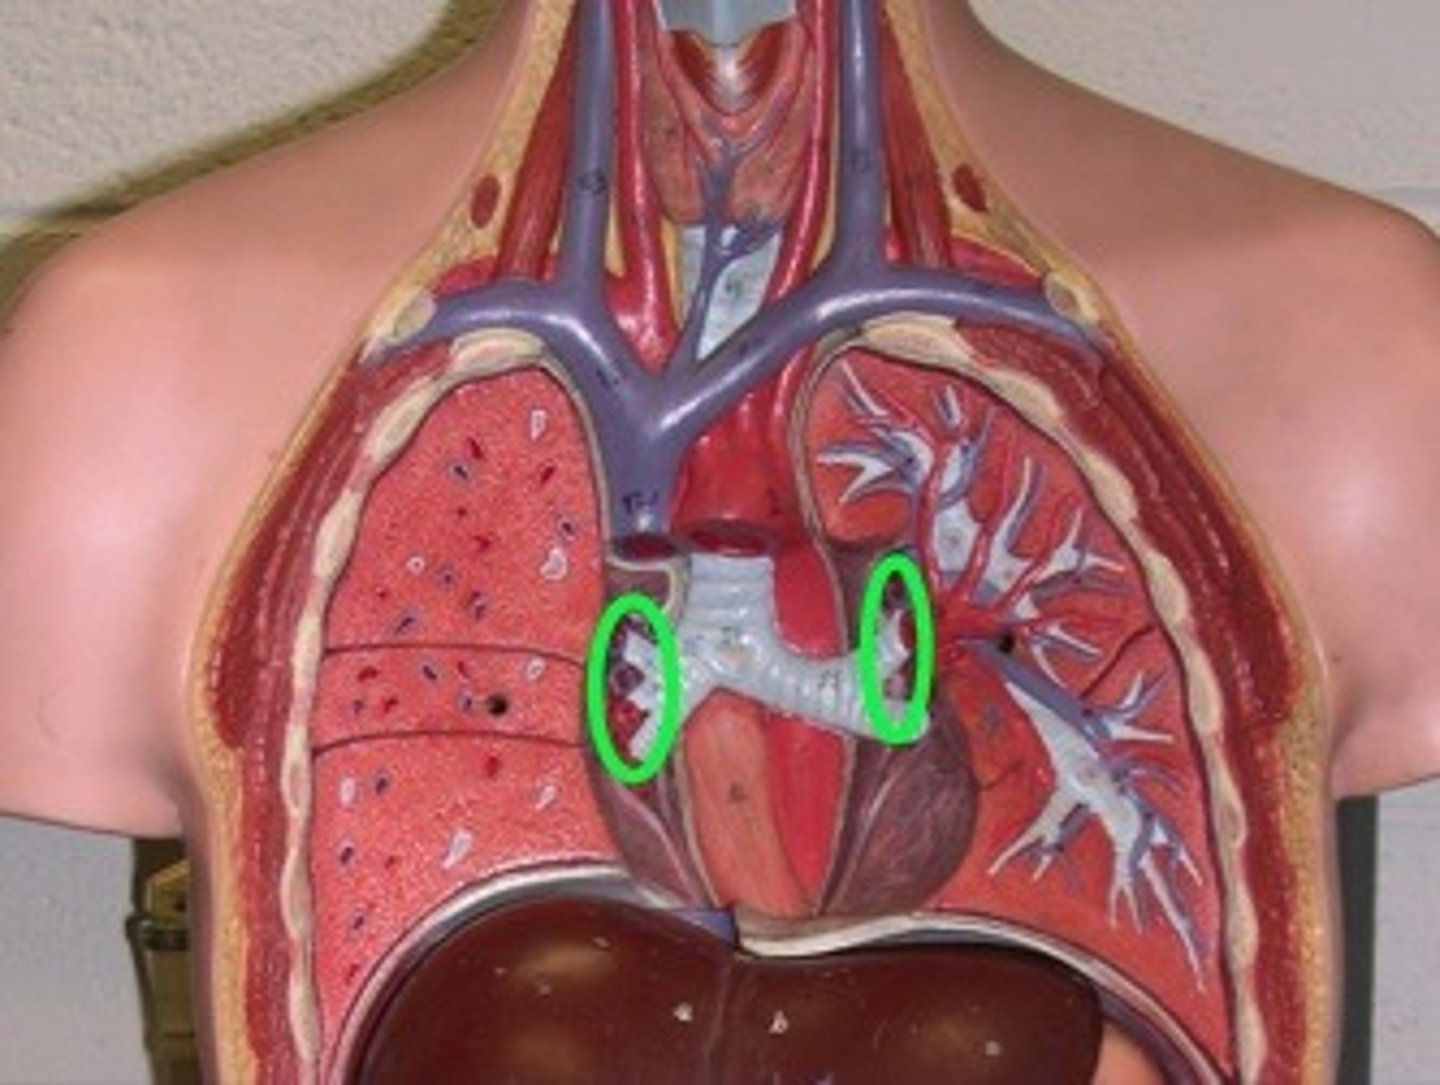

hilum

concave structure on the mediastinal surface of the lungs where blood vessels, lymphatic vessels, nerves, and a bronchus enter the lung

pleurae

thin, double-layered serosal membrane that divides thoracic cavity into two pleural compartments and mediastinum

parietal pleura

outermost layer of the pleura that connects to the thoracic wall, mediastinum, and diaphragm

visceral pleura

innermost layer of the pleura that is superficial to the lungs and extends into the lung fissures

pleural cavity

space between the visceral and parietal pleurae

pleural fluid

substance that acts as a lubricant for the visceral and parietal layers of the pleura during the movement of breathing

lingula

a tongue-like extension of the left superior lobe projects anteriorly over the heart

cardiac notch

a concave space on the left lung in which the heart lies